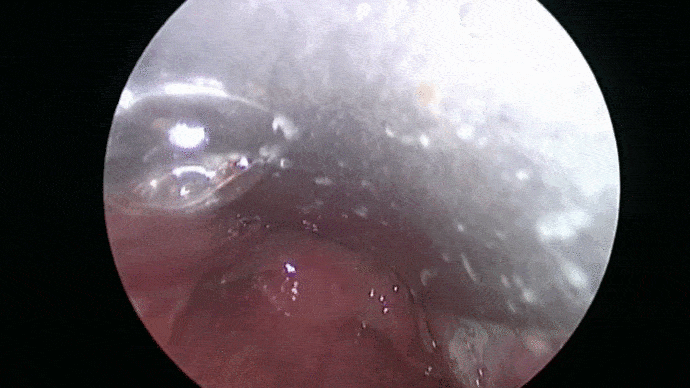

Les troubles de la voix sont analysés puis les cordes vocales sont examinées grâce à système optique afin de proposer une prise en charge adaptée.